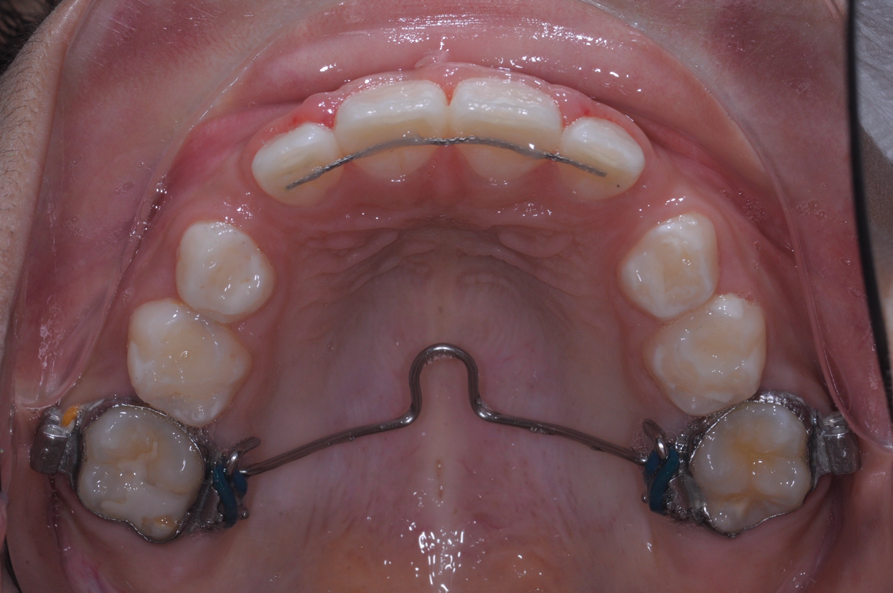

Fig 3. Initial situation of case involving an impacted maxillary right central incisor, frontal view (Fig 2) and occlusal view (Fig 3).

Figure 3

The following case illustrates the complete surgical/orthodontic treatment sequence for an impacted maxillary right central incisor. An 8½-year-old patient presented with a chief complaint of crowded teeth. The maxillary left central incisor was the only erupted incisor at the time of consultation (Figure 2 and Figure 3). Crowding was clinically diagnosed visually by the prominence of the unerupted right central incisor in the vestibule, and this was confirmed with a panoramic radiograph (Figure 4).

The maxillary right permanent centralincisor had a delayed eruption of 1½ years compared to its homologous incisor, and it was anteriorly displaced due to insufficient space in the premaxilla. Removal of the maxillary deciduous canines was indicated to unravel the crowding. An apically positioned flap of the impacted right central incisor was made to facilitate its eruption (Figure 5 and Figure 6). The case was worked up to plan an active phase l treatment, consisting of palatal expansion and the use of sectional fixed appliances in the upper arch. A transverse deficiency without posterior crossbite was identified, and therefore palatal expansion with a bonded expander was planned to widen the premaxilla (Figure 7 and Figure 8). A two-by-four fixed appliance system (brackets in the four maxillary anterior teeth and bands on the maxillary first molars) was used to align the maxillary teeth. The gingival margin of the retained maxillary right central incisor was slightly more apical than the left one, which erupted as expected (Figure 9 and Figure 10). Figure 11 shows a panoramic radiograph taken after completion of phase 1 treatment.